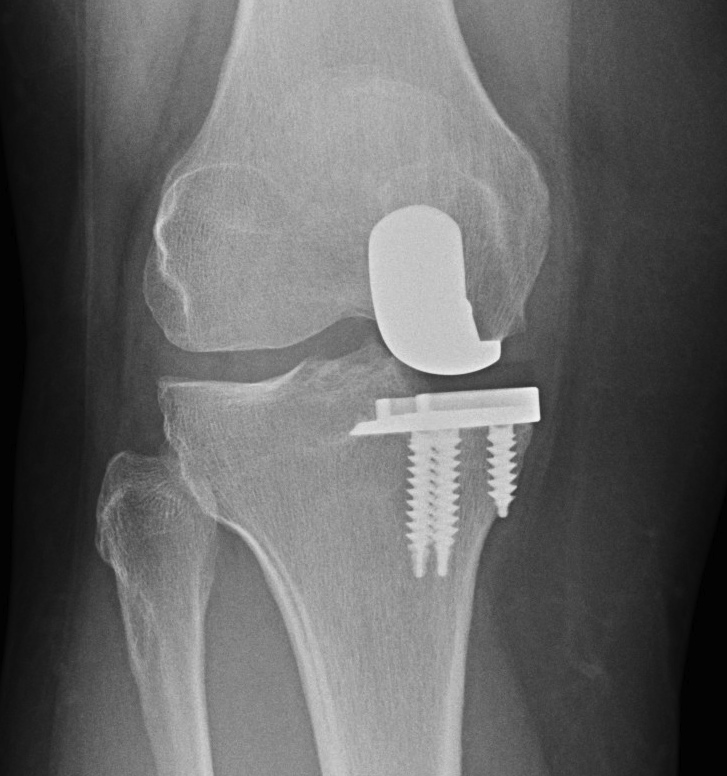

Patient 2